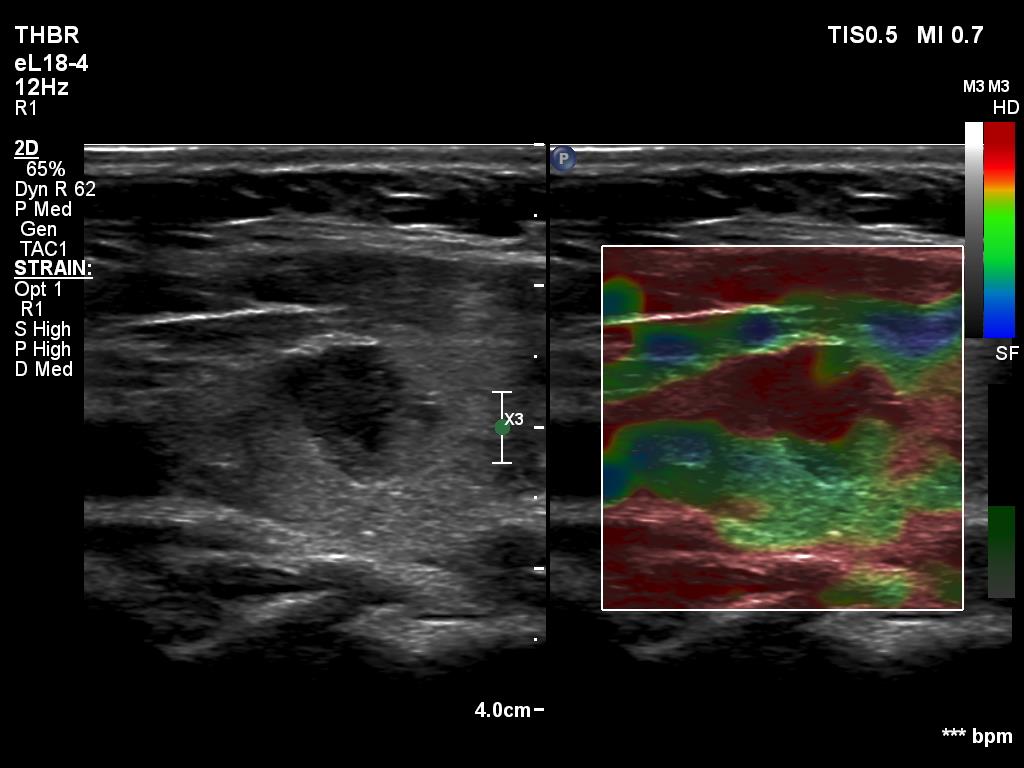

Left lobe, longitudinal scan, elastography. The lesion proved to be very hard.